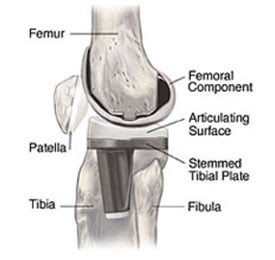

During the main phase of the operation, the surgeon cuts and removes cartilage and some bone from the upper part of the tibia and lower sections of the femur. The femoral sections removed are two knobby protuberances called the femoral condyles. The tibia and femur are then capped with metal implants to create new surfaces for the joint. The surface of the femoral component mimics the shape of the original femoral condyles. If the kneecap has also degraded, the surface on its underside may also be cut away and replaced with a polyethylene (plastic) implant.

Fixed-bearing knee implant with a polyethylene articulating surface (plastic tray) sandwiched between the metal tibial implant and metal femoral implant.

Side-view illustration of a knee with a fixed-bearing knee implant in place.